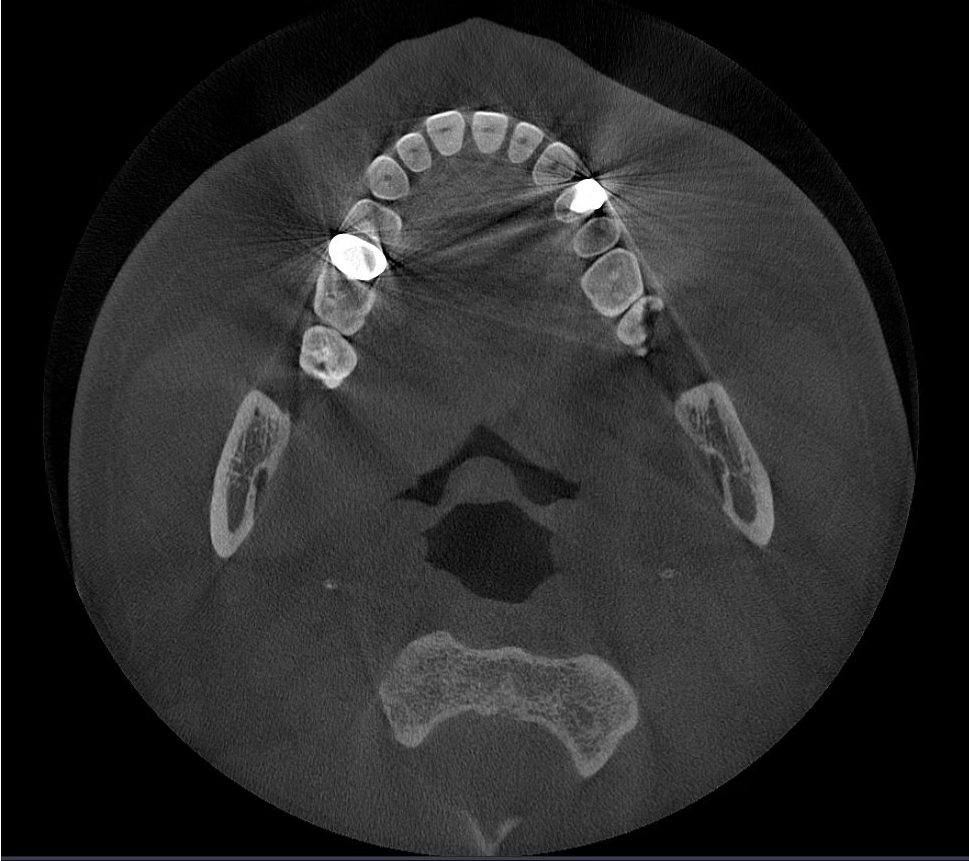

La tecnología IA

Borra los artefactos metálicos y restaura con precisión las estructuras dentales, las coronas metálicas y los implantes basados en principios matemáticos.